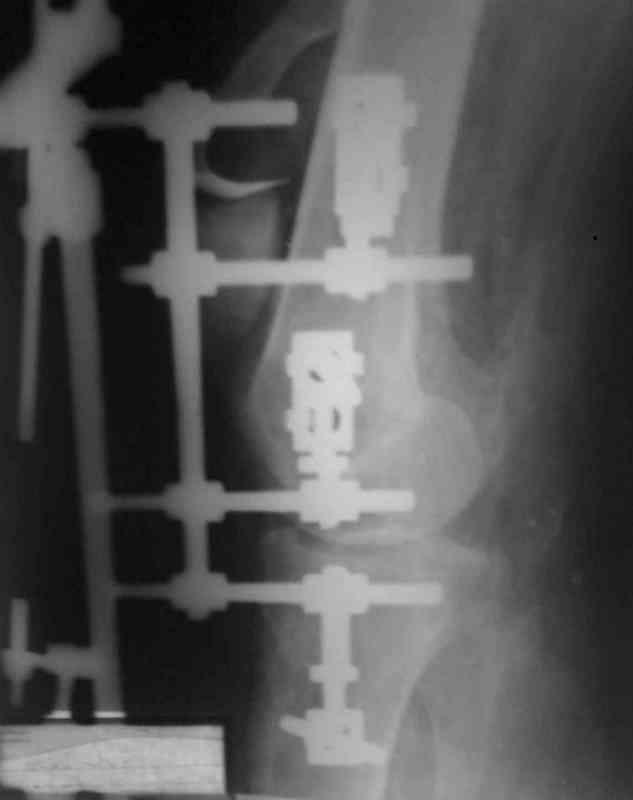

Снимки прошлых публикации из моего Power point

При пользовании стержневых наружных фиксаторов,

надо придерживаться правила проведения стержней подальше от зоны, на бедре лучше накладывать стержни косо передне-латерально, между брюшками прямой и vastus lateralis, а на голени по передне-медиальной поверхности большеберцовой кости, где отсутствует мышцы, иначе

восстановление движения в суставе тяжелее из-за

прошитых мышц спицами или стержнями аппарата.